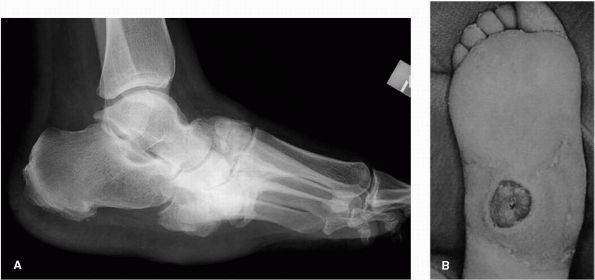

FIGURE 21-17. A rheumatoid foot. (A)

Preoperative radiograph of typical rheumatoid changes with a severe hallux valgus deformity and subluxation and dislocation of the lesser metatarsophalangeal joints. (B) Reconstruction using an arthrodesis of the first metatarsophalangeal joint and arthroplasties of the lesser metatarsophalangeal joints. |

![]() |

FIGURE 21-18.

The presence of a long second metatarsal in the forefoot metatarsal cascade results in excessive pressure beneath metatarsal head, which may predispose to “metatarsalgia” pain. |